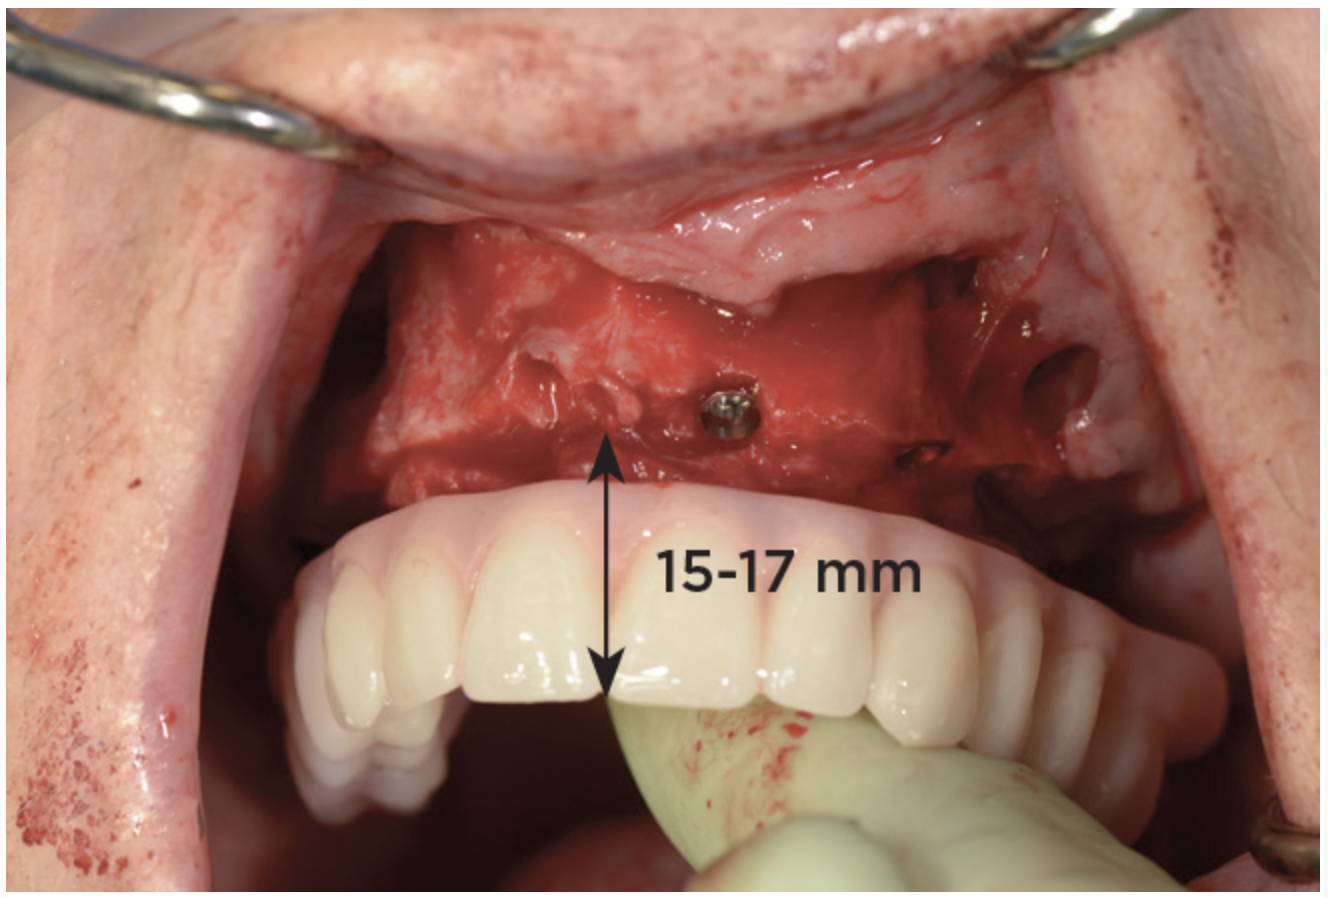

Fig 19. Patient smile shown 3 years post-treatment.

Figure 19

Fig 20. Patient intraoral condition 3 years following delivery of maxillary and mandibular All-on-4 definitive prosthesis.

Figure 20

Dental rehabilitation with the All-on-4 treatment concept is often a life-changing event for edentulous and terminal dentition patients that results in unprecedented quality of life improvements (Figure 17 through Figure 20).